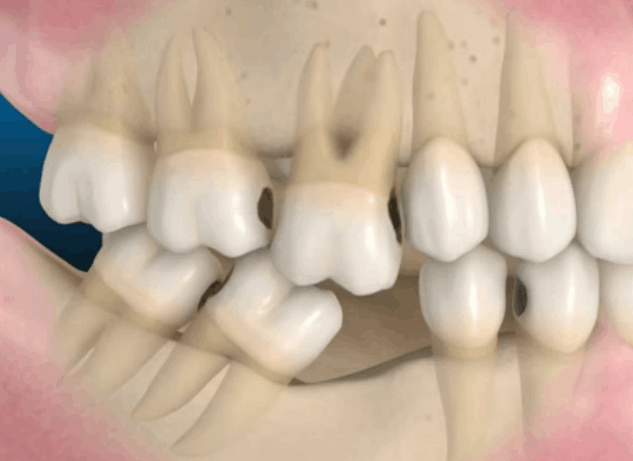

Estas guías son diseñadas digitalmente a partir de estudios previos de cada paciente, lo que nos permite planificar con precisión la posición, angulación y profundidad del Implante Dental. Gracias a esta tecnología, logramos intervenciones más seguras, rápidas y predecibles.

La colocación de Implantes Dentales por medio de cirugía mínimamente invasiva reduce significativamente la necesidad de cortes amplios o suturas, lo que se traduce en menos molestias postoperatorias, menor inflamación y una recuperación más rápida para usted.